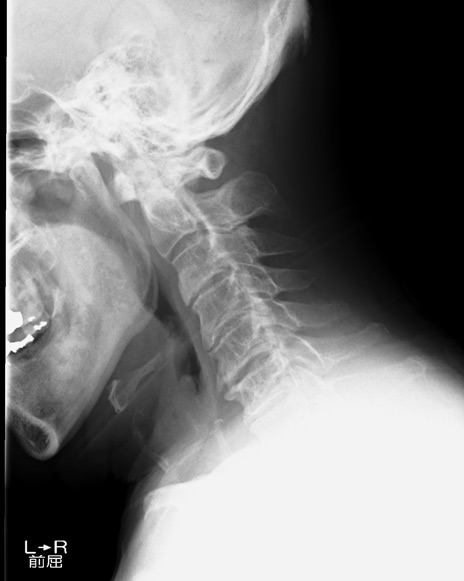

【整形】TIPS症例7 頚椎レントゲン 側面像(屈曲)

側面像(伸展)